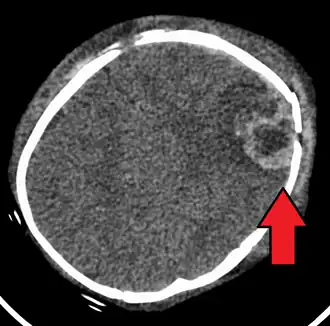

Синдром детского сотрясения (СДС) (синдром встряхнутого ребёнка, SBS) — комплекс органических нарушений, которые могут возникнуть, если организм ребёнка испытает сотрясение. Незафиксированная головка болтается, из-за чего разрываются мембраны клеток головного мозга, и повреждается мозг в целом — кровоизлияния под оболочки головного мозга (без наружных признаков повреждения). СДС служит одной из основных причин гибели младенцев. СДС не обязательно возникает из-за грубого обращения с малышом. Он может случиться во время игры с малышами, например, когда взрослые подбрасывают ребёнка высоко в воздух или слишком резко его встряхивают, при несчастных случаях на транспорте в результате наезда на машину сзади. Впервые СДС был обнаружен нейрохирургом Н. Гутхельгом в 1971 году. В 2003 году в Эдинбурге прошёл первый конгресс по СДС. Первый судебный процесс по СДС был в Швейцарии в 2003 году.

«Травма головы, возникшая из-за неосторожного обращения с ребёнком, является одной из основных причин заболеваемости, инвалидизации и смертности у новорождённых детей.

У большинства грудных детей, пострадавших от травмы, возникшей в результате сильного встряхивания, сохраняются стойкие неврологические нарушения, и более 25 % их умирает»